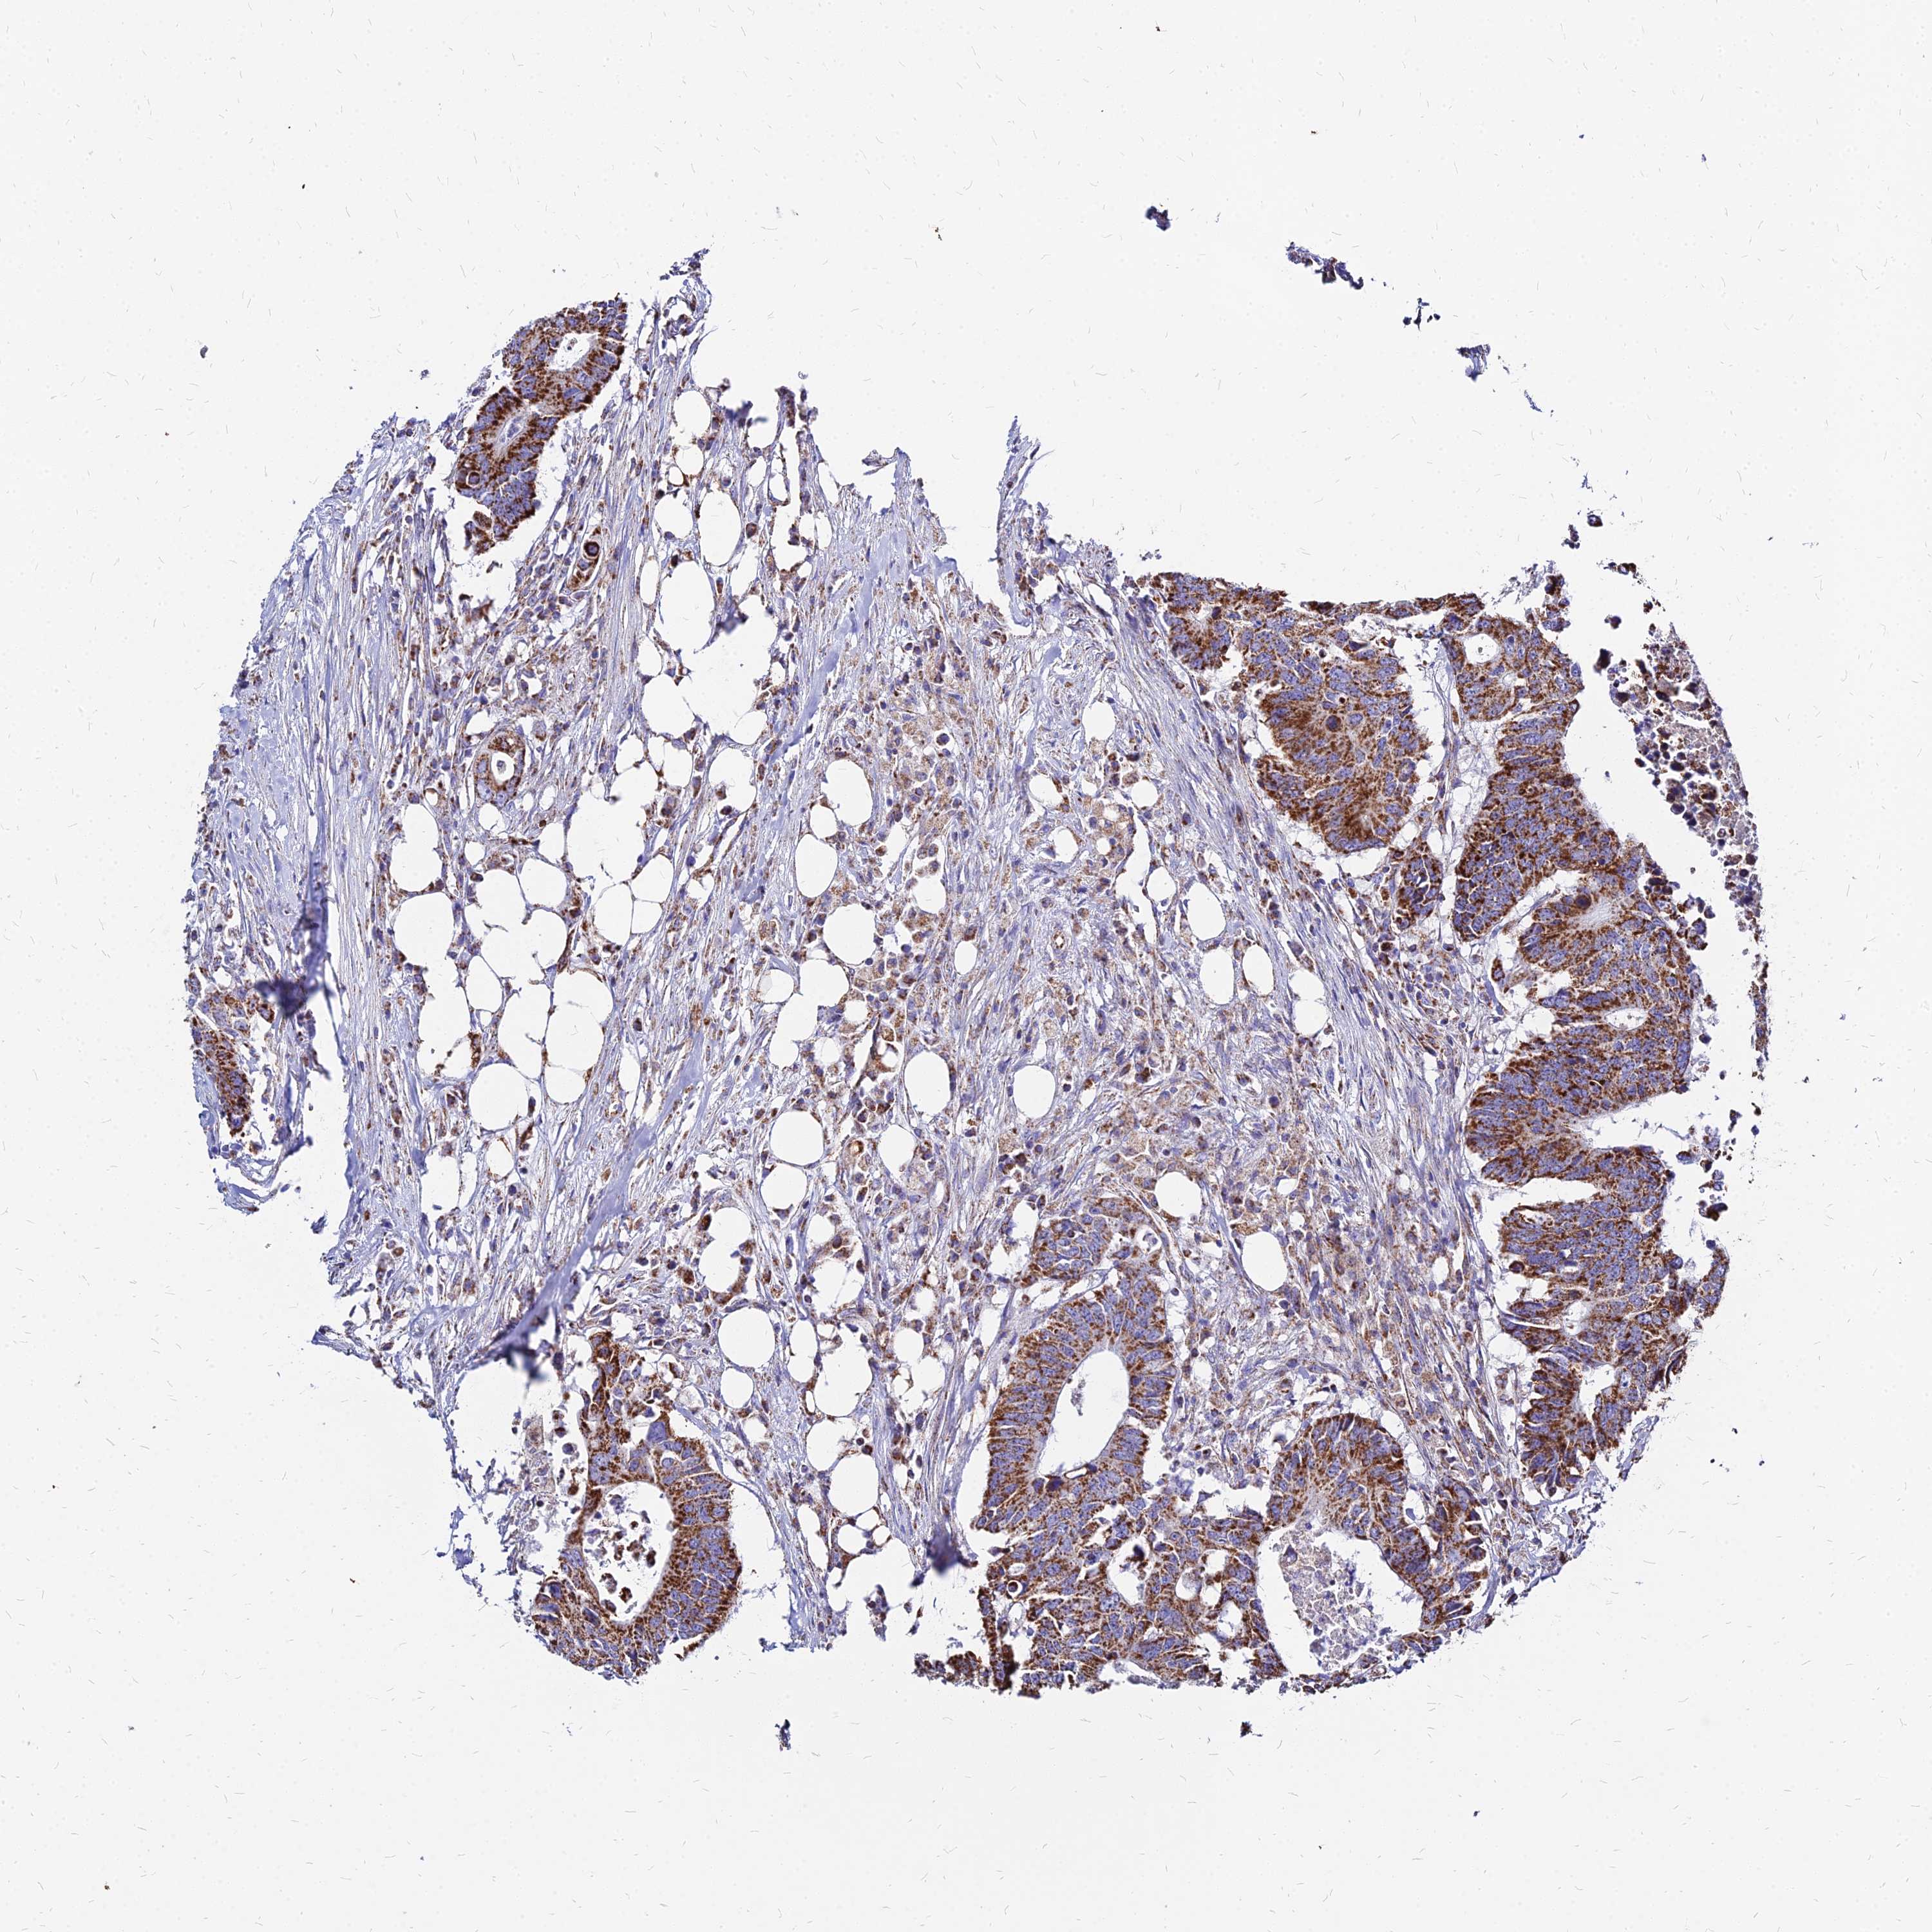

CANCER COLORECTAL CANCER Show tissue menu

Colorectal cancer

Human cancer

Colon adenocarcinoma